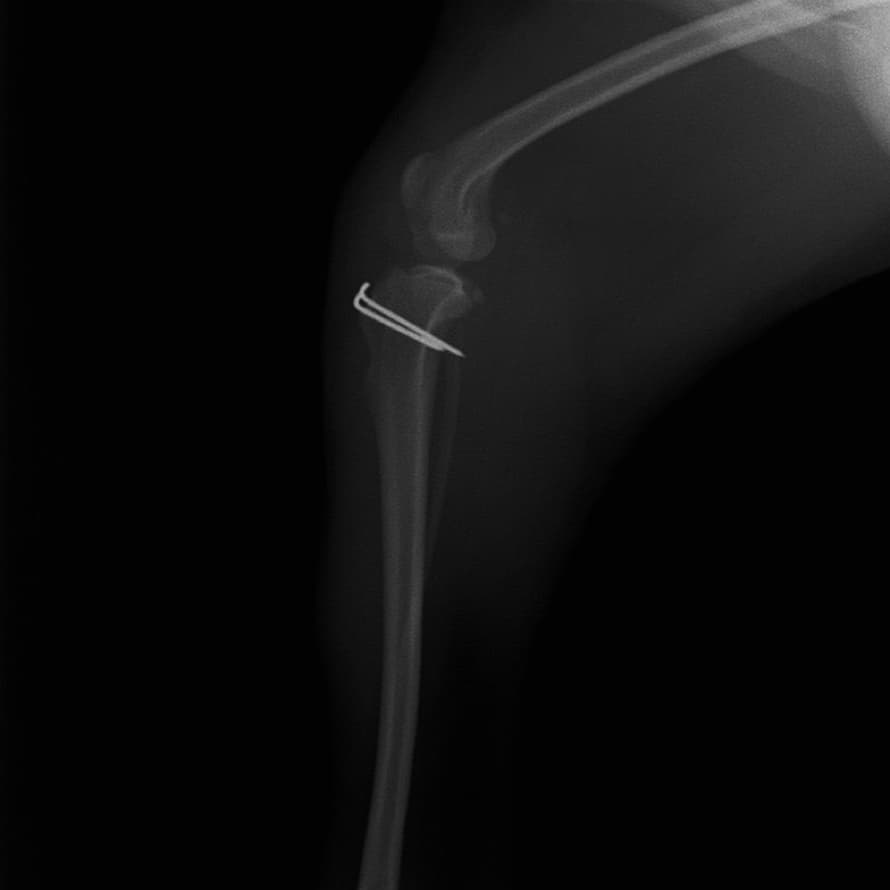

■ 症例24 キャバリア 7か月

左右膝蓋骨内方脱臼(左:グレードⅣ 右:グレードⅢ)

以前から左右後肢の跛行が認められ、整形外科学的検査・レントゲン検査により左右の膝蓋骨脱臼が認められた。症状が重度である左膝の膝蓋骨脱臼整復術を行った。外科手技は縫工筋及び内側広筋の解放、脛骨粗面の外側転位、滑車ブロック形造溝術、内外側関節方の縫縮を実施した。術後一か月時点で、左の膝蓋骨は安定しており経過は良好である。

本症例は成長期における重度の膝蓋骨脱臼であり、術後の再発の可能性もあるため、経過をしっかりと観察していく必要がある。また、今回手術を実施していない右膝に関しても経過を観察し、手術を検討していくこととする。